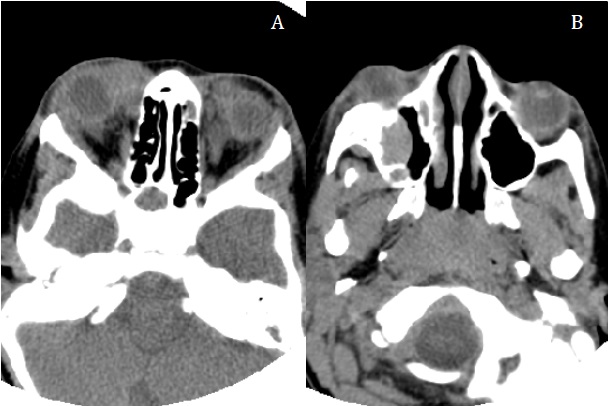

La exploración física fue normal, salvo por la presencia de una proptosis bilateral, con marcado exoftalmos derecho. Tras ser valorado por el servicio de oftalmología, se decidió realizar una tomografía computarizada craneal ante la sospecha de una infiltración de probable origen tumoral. En esta se observaron masas orbitarias bilaterales extraconales, en el techo de ambas órbitas y en el seno maxilar derecho, con probable afectación ósea asociada, presentando, además, ocupación del seno esfenoidal derecho y algunas celdillas etmoidales (Fig. 1). A la vista del resultado, se plantearon los diagnósticos de infiltración por leucemia, linfoma o histiocitosis de células de Langerhans, y se decidió ingresar al paciente para completar el estudio.